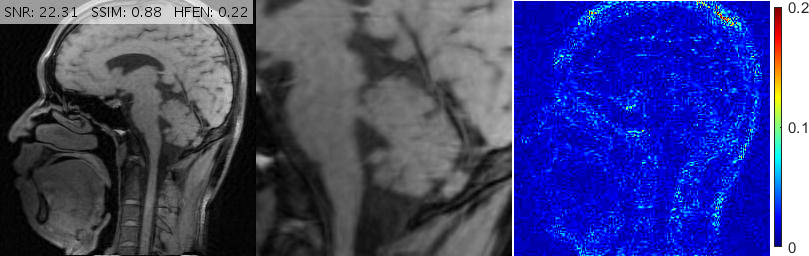

In clinical imaging, the same slice might be acquired in different rotational orientations. For instance, a slice might be imaged in an upright position in one acquisition, but the same slice might be acquired in a rotated position in another experiment. It is ideal to have a robust regularization term that reconstructs the rotated image as if it were acquired in the upward orientation, with no loss of diagnostic value. The rotation-invariance (or isotropy) of RITV was theoretically established in Theorem 2.1. In this subsection we investigate the implication of that result in a rotated imaging setup.

We select a -sized -weighted axial brain scan from our collection along with a 20% Cartesian mask. In order to simulate upright and rotated image acquisition sequences, we consider two setups:

-

1.

The reference image is in upright orientation. The FFT of the image is taken, then the sampling mask is applied (see Fig. 5 (1)).

2.

The reference image is rotated from upright position, say, by (counterclockwise). The FFT is taken, then the sampling mask rotated by the same is applied (see Fig. 5 (2)).

We investigate the performance of RITV compared to TV and TGV in these setups. The implementation of RITV is the same as described in Algorithm 1 and Subsection 3.1, with the only difference being the removal of the BM3D term (and readjustment of to ), since we wish to observe the performance of RITV only. TGV is implemented using the algorithm and parameters described in [7]. TV is also implemented with the same algorithm, with optimized to . TV and TGV algorithms run for 500 iterations while the RITV runs for 200.

Fig. 6 depicts the reconstruction results for above setups. As attested by the magnified views and error metrics inserted to the top of each reconstruction, TV and TGV significantly degrade the reconstructed image in the rotated setup while RITV gives a remarkably consistent and high-quality result which is hardly distinguishable from the upright solution (note that HFEN and SSIM indices do not change in RITV after rotation). Of course, the upright and rotated directions are only chosen relatively and can always be swapped, nevertheless, the point is TV and TGV fail in at least one of the orientations while RITV succeeds in both. Note that if the selected MR image and Cartesian mask are denoted by and respectively, then a simple machine-aided computation shows that . Therefore, even though the norm-preserving assumption of Theorem 2.1 does not hold true in this experiment (and in fact in many practical situations), the result of RITV is still incredibly isotropic.